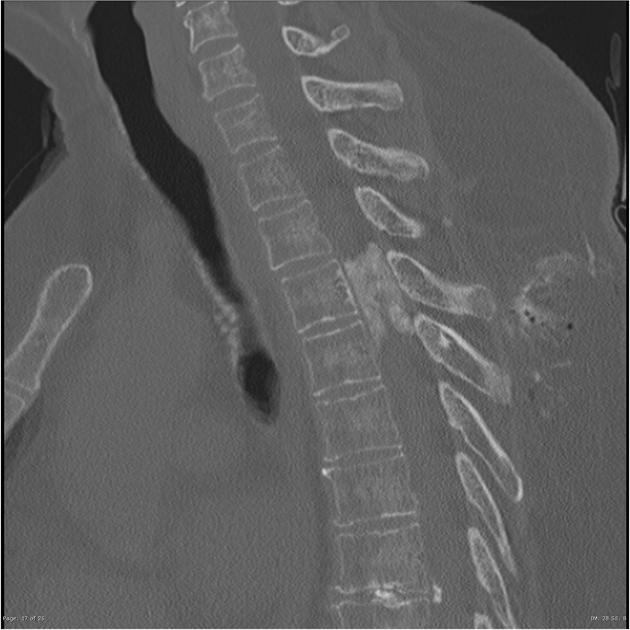

位于硬膜内的脊柱肿瘤发病率为每年每10万人3 ~ 10例,其中硬膜内髓外肿瘤占椎管内肿瘤的2/3,其中脊髓脑膜瘤占脊髓肿瘤的25-46%。它们由与神经嵴细胞不...